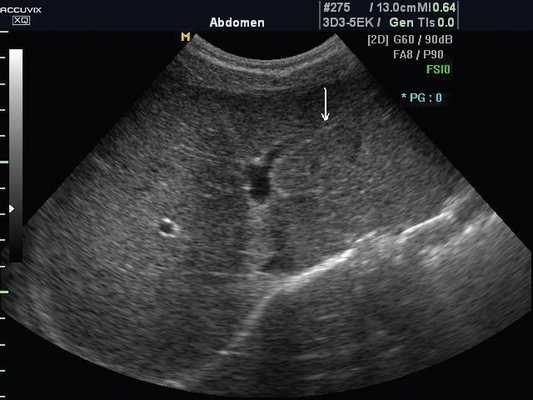

Эхографическая картина нормальной печени. В норме печень ребенка гомогенна. Характер обработки сигнала выбирают в зависимости от цели исследования (рис. 1а, 1б). Капсула печени тонкая, эхогенная. Эхогенность паренхимы печени выше, чем паренхимы коры почек. Медуллярная ткань почек темнее паренхимы печени. Вентральный край печени тонкий, острый. При увеличении размеров печени он закругляется. Частым показанием к проведению УЗИ является подозрение на увеличение размеров печени. Существует много формул для расчета размеров печени, в том числе волюметрические. Последние используются в основном в научных целях или в специализированных клиниках. Размеры и конфигурация печени достаточно вариабельны. При рутинных исследованиях размеры печени можно оценивать качественно. Правая доля печени распространяется до нижнего полюса почки, но если существует риделевская долька (вариант нормы), то несколько ниже. У детей 1 года жизни левая доля при поперечном сканировании распространяется за срединную линию, у старших детей - до аорты. При гепатомегалии левая доля простирается вплоть до селезенки, сдвигая ее вниз. Смещение селезенки может служить причиной ошибочного заключения о спленомегалии. Таким образом, печень состоит из правой и левой долей. Кроме того, имеется и хвостатая доля. Доли печени делятся на сегменты. Упрощенно - правая доля имеет передний и задний сегменты (граница - правая печеночная вена). Левая доля состоит из медиального и латерального сегментов (граница - левая печеночная вена). Каждый сегмент имеет свое кровоснабжение. Поэтому при синдроме Бадда-Хиари (обструкция печеночных вен) сегменты увеличиваются в размерах, их эхогенность возрастает. Знание сегментов печени важно и для точной локализации объемных образований.

а) Эхограмма печени 12-летнего подростка в обычном режиме. Обратите внимание, что даже в 12-летнем возрасте круглая связка печени (стрелка), отходящая от левой части воротной вены, имеет каналикулярный вид (просвет внутри).